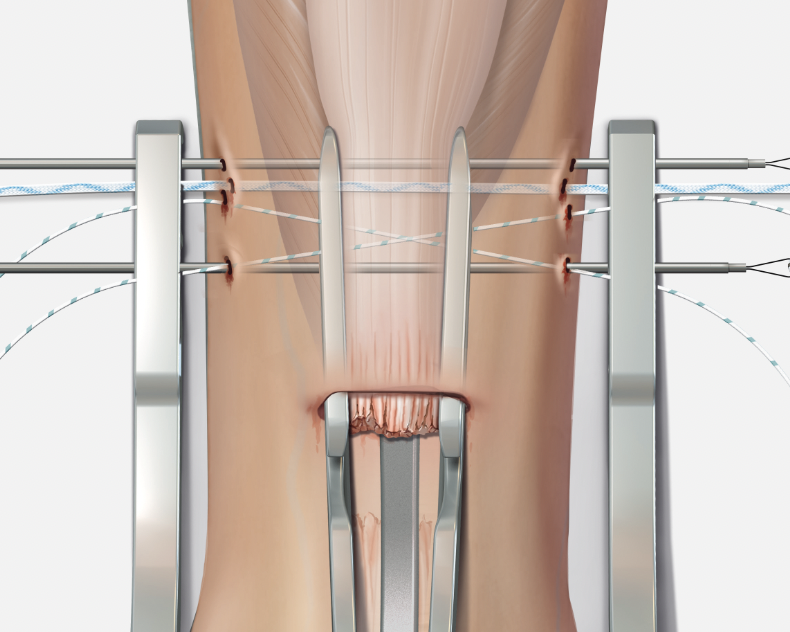

Minimally invasive repair

Percutaneous suture technique

Arthrex PARS

Vumedi percutaneous repair video

Calcaneal anchor technique

Arthrex Speedbridge technique

Vumedi Arthrex Speedbridge in calcaneum

Vumedi stryker anchors in calcaneum video